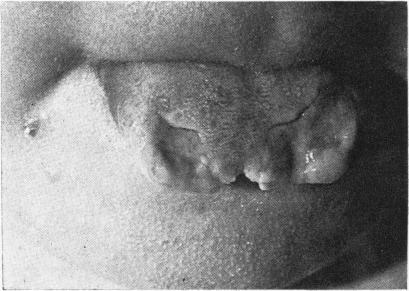

Congenital sensory neuropathy with anhidrosis.

Arch Dis Child. 1968 Feb;43(227):124-30. doi: 10.1136/adc.43.227.124.